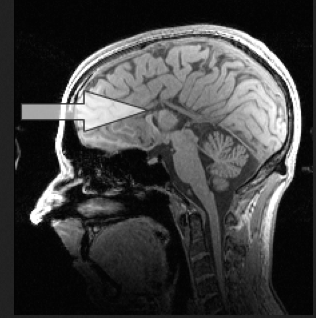

Agenesis literally means a (not) – genesis (developed). This is a condition in which the corpus callosum of a fetus does not develop or only partially develops. If the corpus callosum does not develop during the critical gestational stage, it will not develop later. In this case the child either has complete agenesis, meaning a complete absence of the corpus callosum, or partial agenesis meaning that part of the corpus callosum developed. Both complete and partial callosal agenesis carry the title of Agenesis of the Corpus Callosum (which abbreviated ACC or AgCC).

Complete Agenesis of the Corpus Callosum – The arrow points to where the corpus callosum should be.